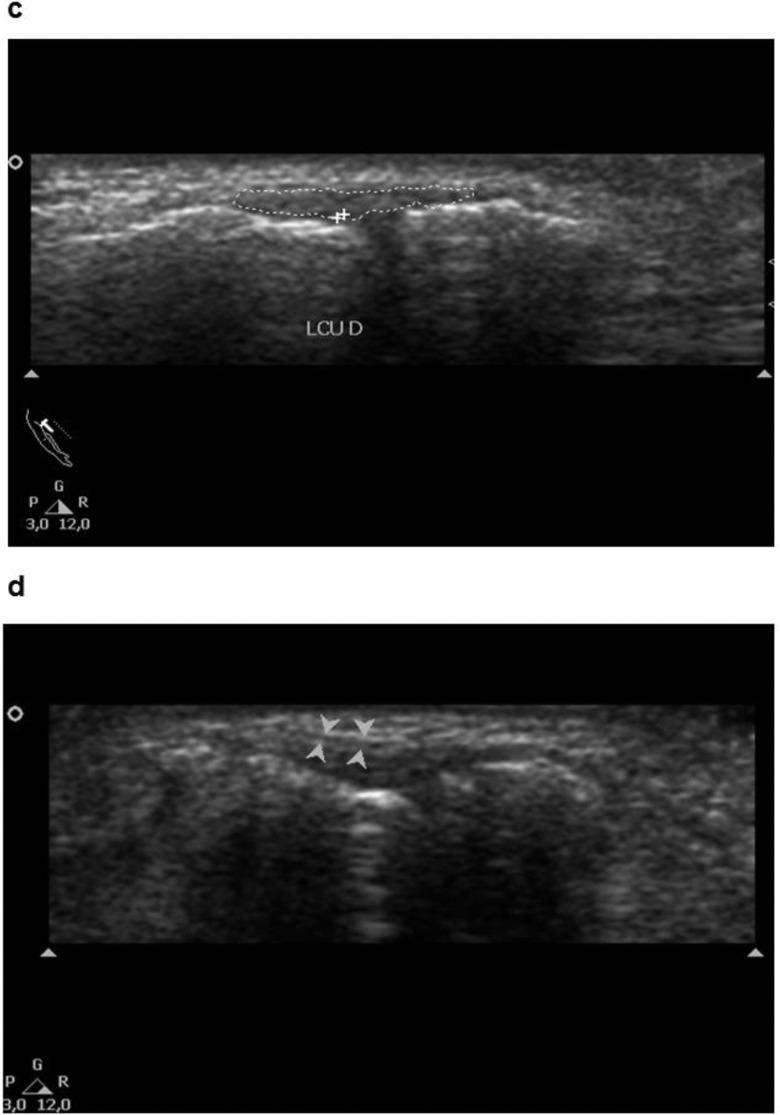

The aim of this study was to perform ultrasonographic characterization of the normal ulnar collateral ligament in different age groups and compare it in men and women and in dominant and nondominant hands.

Forty right-handed volunteers in the age groups 20-30, 31-40, 41-50, and 51-60 years without a history of trauma or surgical procedure in the studied joint were evaluated. The studied parameters were ligament length, greatest ligament thickness, ligament longitudinal section area in the longitudinal plane, distance from the aponeurosis of the adductor muscle to the metacarpal head surface and joint opening at rest and under abduction stress.

The results indicated that the mean values of all parameters had minor variations with age, hand dominance, and gender and were slightly higher in men than in women and in the dominant hand than the nondominant hand. However, a statistically significant difference was observed between the joint opening at rest and under stress. In terms of age, there was a small but nonsignificant decrease in the values, likely because of the natural aging process.

The low variability in the evaluated parameters indicates that large differences between sides or genders are not to be expected. A greater change is likely to indicate a pathological situation.